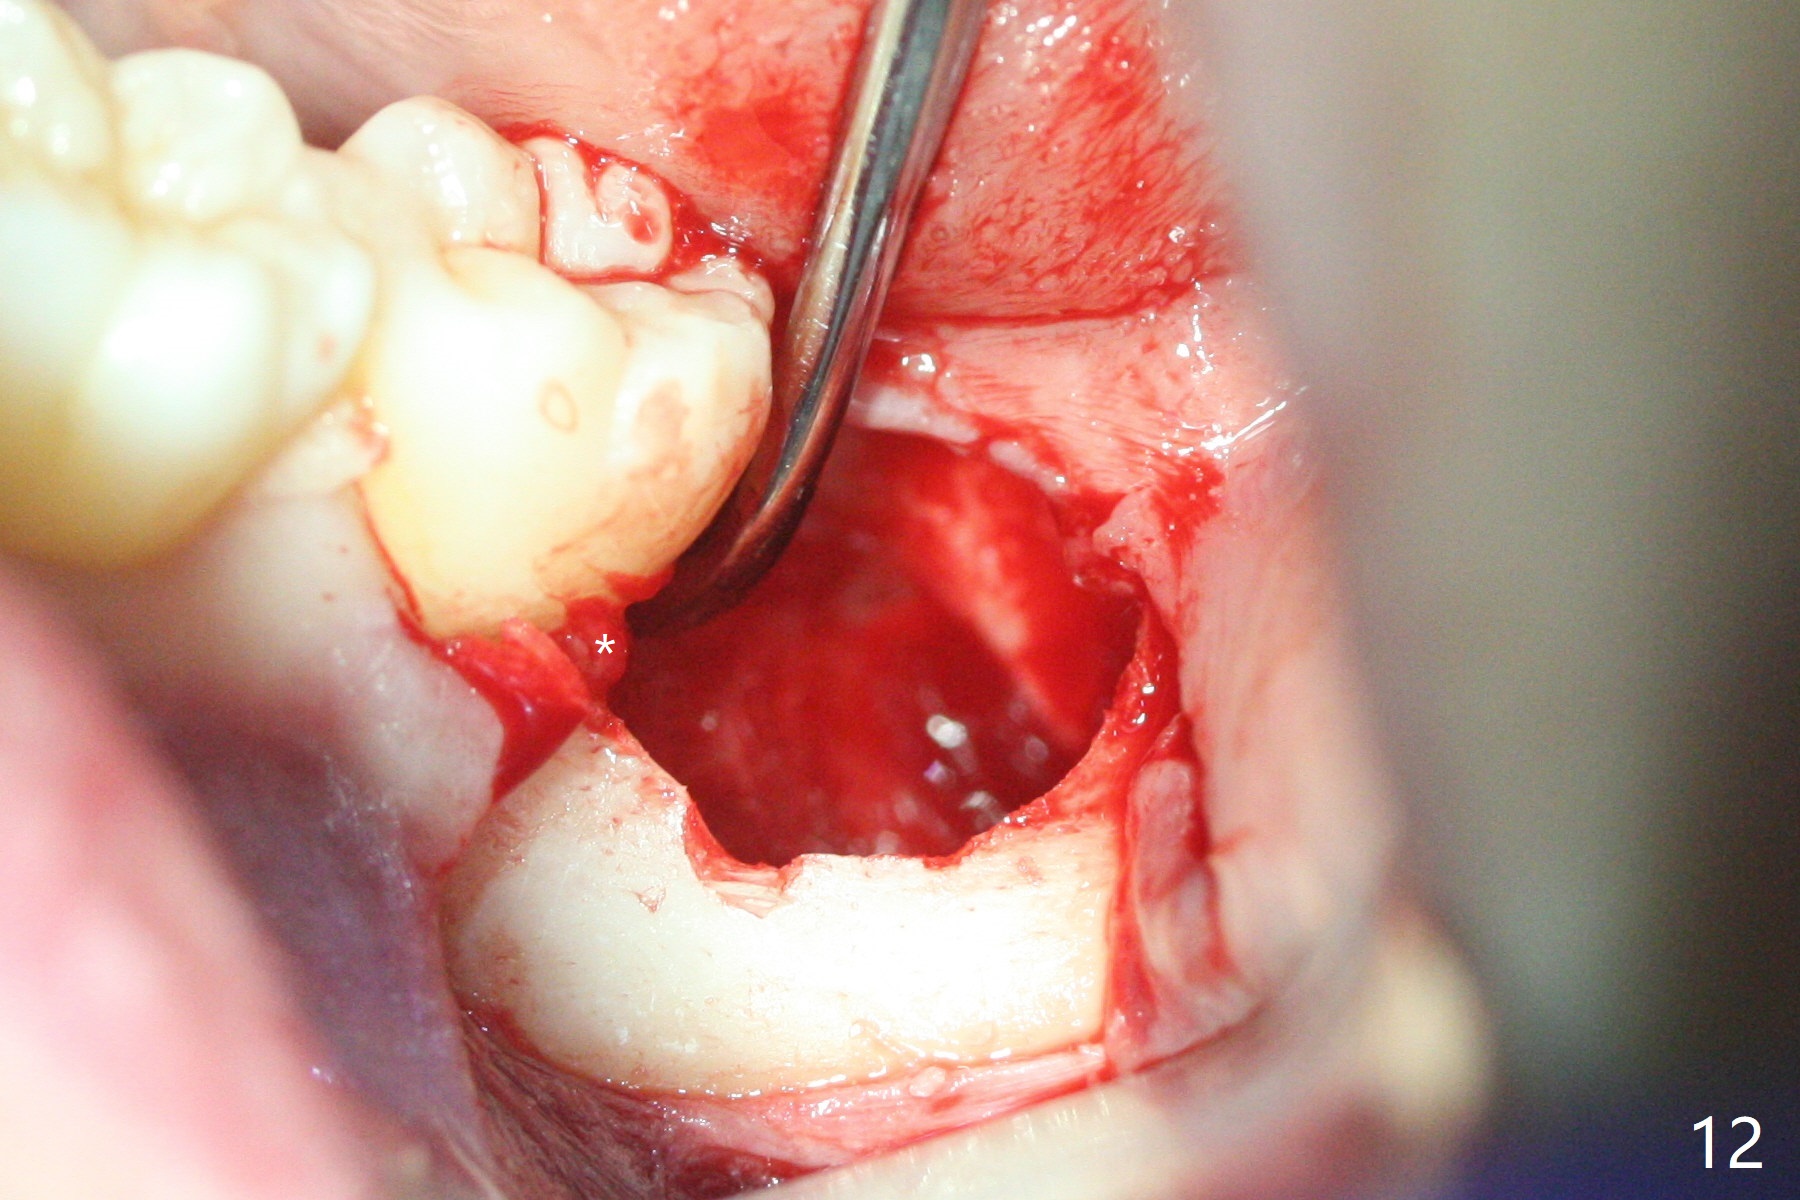

In fact the tooth #32 is extracted first; the defect involves the distobuccal aspect of the tooth #31 (Fig.4 *). An intraop PA is taken after extraction to confirm whether a broken surgical fissure bur tip retains or not; the distal lamina dura of #31 is low (Fig.5 *). It is expected to increase after cocktail bone graft (Fig.5' arrow). As planned, the bone cement (Fig.6 C) and allograft (G) are placed in the distal and mesial portions of the socket; between them is Osteogen Plug (O). Another piece of Osteogen Plug (as collagen membrane for bone graft) is placed on the top of the socket before suturing with 4-0 Plain Gut (Fig.7,7' O). Also note the bone graft being placed distobuccal (CT study) to #31 (Fig.7' red dashed line) to reduce possibility of future periodontitis. The patient returns 15 days postop with chief complaint of mild pain since extraction, although the wound looks normal. The transverse cortex connecting to the lamina dura (Fig.5 *) is obliterated when allograft is placed (Fig.7 G). The part of the graft remains in place 1 month postop (Fig.9) in spite of wound dehiscence (Fig.8). The bone graft loss is indicated by the fact of the reappearance of the transverse cortex (Fig.9). In the same appointment, the tooth #17 (Fig.10) is being extracted (Fig.11), leaving a defect mesiobuccal (Fig.12 *) to distal (curette). Part of Osteogen plug (Fig.13 O) is stretched to cover the mesially placed allograft (Fig.14 G). One quarter of Collagen plug is placed over the Osteogen plug (Fig.13 O) before 4-0 PGA suturing. There is bone regeneration 1 year postop (Fig.15,16).